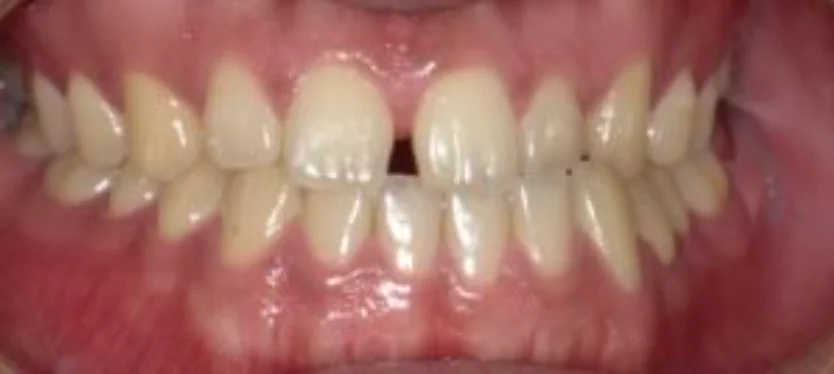

Before

After

正中離開(すきっ歯)(50代女性)

即日 / 総額110,000円リスク・副作用:噛み合わせの変化や歯ぎしりで、樹脂が欠けてしまうことがあるため、ナイトガードの継続的使用と定期検診での噛み合わせの確認をしっかり行う必要があります。